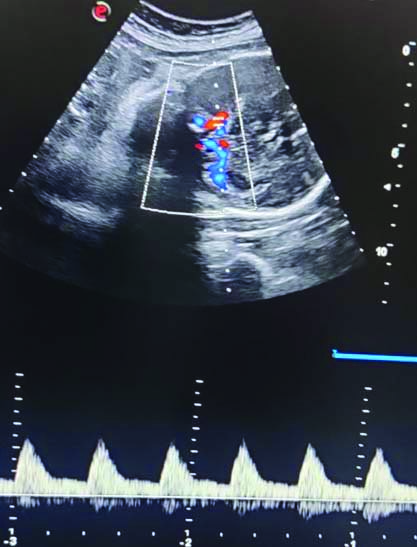

All enrolled women underwent Doppler ultrasonography to assess the MCA PI. The ultrasound machine, Philips 11XE, equipped with a transabdominal convex multi-frequency probe (2-5 MHz) with colour/power Doppler, was used in this study. For the MCA Doppler, the ultrasound probe was placed on the abdomen. An axial section of the foetal brain showing the thalami and sphenoid bones was obtained, magnified, and the MCA PI was measured as explained by Romero R and Hernandez-Andrade E [Table/Fig-1] [10]. Three measurements the MCA PI were obtained, and the mean of these three values was taken.

Measurement of MCA Doppler PI.